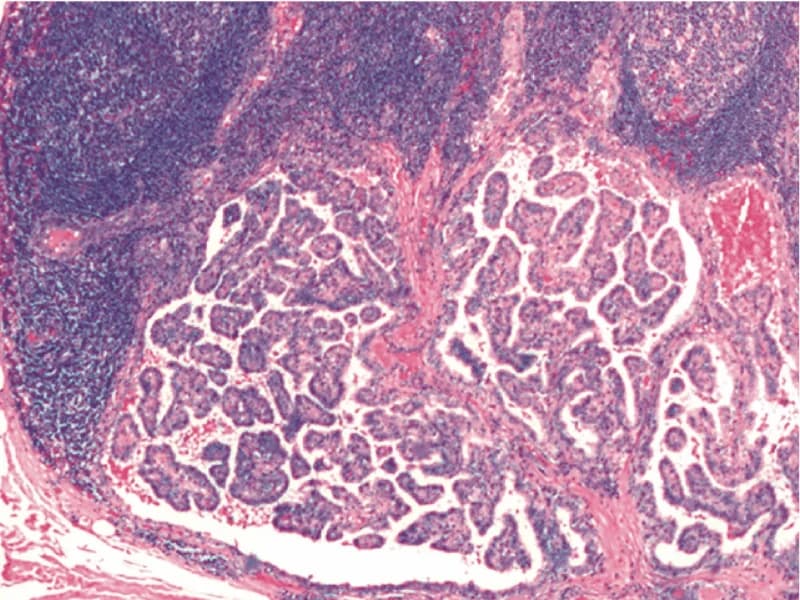

Doença de Plummer, também conhecida como bócio multinodular tóxico, é uma condição caracterizada pela presença de um ou mais nódulos autônomos na glândula tireoide que produzem hormônios tireoidianos em excesso, levando ao hipertireoidismo. Diferente da Doença de Graves, que é uma doença autoimune afetando toda a glândula tireoide, a Doença de Plummer envolve nódulos específicos que funcionam independentemente do controle normal do corpo sobre a tireoide. Sintomas do hipertireoidismo associados à Doença de Plummer podem incluir perda de peso, palpitações, tremores, intolerância ao calor, aumento da sudorese, fadiga, fraqueza muscular, alterações no ciclo menstrual, e aumento do apetite. Pode também ocorrer um aumento visível da tireoide, conhecido como bócio. ▶Dr. Jônatas Catunda Cirurgião de cabeça e pescoço CRM 14951 RQE 8522 ▶Esse canal é meramente educacional. Não deve ser utilizado para realizar autodiagnóstico ou auto tratamento! ▶Respeito todas as resoluções do Conselho Federal de Medicina - os vídeos têm somente caráter de prestar informações de fins estritamente educativo e não são divulgados endereço ou telefone de consultório, clínica ou serviço. Seja membro do canal e veja vídeos exclusivos: https://www.youtube.com/channel/UCpL7uBcRElpdP7yEb-9vcgA/join Inscreva-se no canal! http://bit.ly/2FfNPIn Site - https://drjonatascatunda.com Instagram - @drjonatascatunda Consulta online - https://drjonatascatunda.com/consultaonline Whatsapp - 85 98107.2268 #tireoide Nesse canal você vai encontrar muita informação de qualidade sobre as doenças da tireoide como hipotireoidismo, hipertiroidismo, câncer de tireoide, nódulos na tireoide. E também sobre temas variados da especialidade cirurgia de cabeça e pescoço com câncer de boca, de laringe, linfonodos aumentados no pescoço! Produzidos por um especialista no assunto, Dr Jônatas Catunda, cirurgião de cabeça e pescoço, professor universitário de Anatomia humana, mestre em cirurgia pela UFC, doutorando pela UFC.